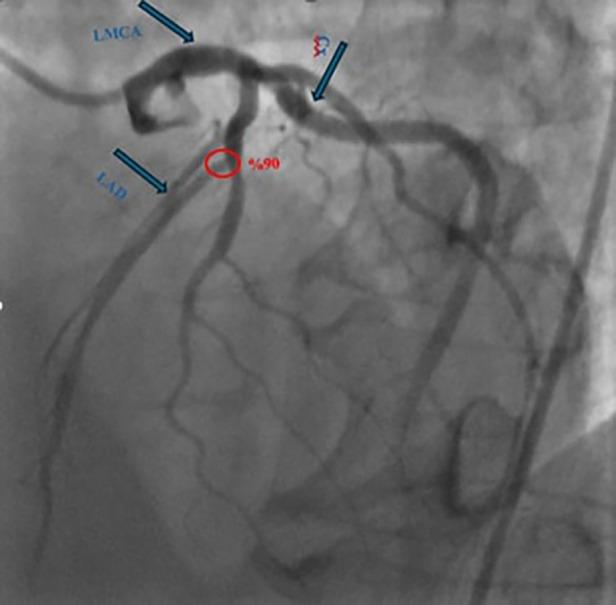

We present two male patients (aged 60 and 61) with ESLD and significant LAD stenosis who underwent simultaneous OPCAB and living donor liver transplantation (LDLT). The first case involved cryptogenic cirrhosis and recurrent variceal bleeding; the second had HBV/HDV-related cirrhosis and hepatocellular carcinoma. In both cases, OPCAB was performed using the left internal mammary artery (LIMA) graft on a beating heart. Subsequently, LDLT was carried out using standard piggy-back techniques. Portal pressure modulation via splenic artery ligation was performed in the first case due to elevated post-reperfusion portal flow. Anesthetic management emphasized hemodynamic monitoring and stability. Both patients were extubated on postoperative day one, discharged with triple immunosuppression, and followed for 6-12 months with preserved cardiac and graft function. A bile leak from the cystic duct anastomosis was encountered in one case.

我们报告了两名男性患者(年龄分别为60岁和61岁),患有ESLD且左前降支严重狭窄,他们同时接受了OPCAB和活体供肝肝移植(LDLT)。第一例患者为隐源性肝硬化并反复静脉曲张出血;第二例患有乙肝病毒/丁型肝炎病毒相关肝硬化和肝细胞癌。在这两例中,均在心脏跳动的情况下使用左乳内动脉(LIMA)移植物进行OPCAB。随后,采用标准背驮式技术进行LDLT。由于再灌注后门静脉血流升高,第一例患者通过脾动脉结扎进行门静脉压力调节。麻醉管理强调血流动力学监测和稳定性。两名患者均在术后第1天拔管,接受三联免疫抑制治疗出院,并随访6 - 12个月,心脏和移植物功能良好。其中一例出现胆囊管吻合口胆漏。